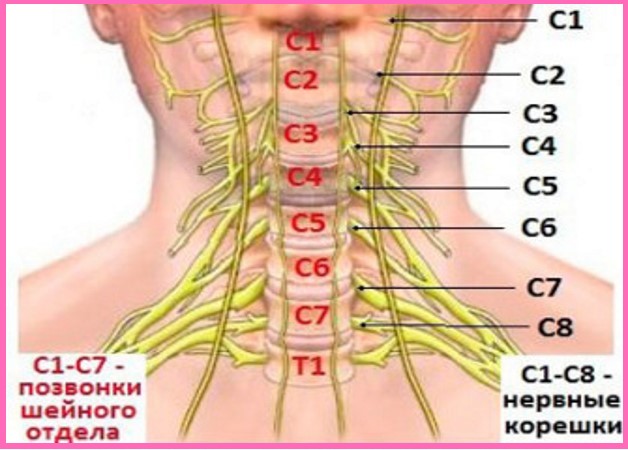

Мне нравится, как об унковертебральных отростках пишет И.Г. Лагунова:

«В 1858 г. Luschka описал в шейных позвонках особые боковые суставы (унковертебральные суставы, или гемиартрозы Лушки). Эти суставы образуются у заднебоковых поверхностей смежных позвонков между полулунными выступами по краям верхней площадки нижележащего и боковыми поверхностями тела вышележащего позвонка. Они встречаются у всех шейных позвонков, начиная с СII—СIII, и в 90% случаев у ThI. Это небольшие суставы с несколько изогнутыми суставными площадками, которые располагаются близко к межпозвоночным отверстиям и примыкают вплотную к фиброзному кольцу межпозвоночного диска. Функционально эти суставы формируются дополнительно к межпозвоночным дугоотростчатым суставам и, образуя единый артикулярный комплекс, в какой-то мере способствует большему объему сгибательно-разгибательных движений в шейном отделе позвоночника. Одновременно они предотвращают скольжение позвонков в боковых направлениях. В последние годы эти суставы в силу особенностей своего расположения привлекли большое внимание с точки зрения их клинического значения. В то же время их происхождение вызывает споры.

Многие авторы считают их не истинными анатомическими суставными образованиями, поскольку в детском возрасте они не выявляются, а компенсаторно возникающими приспособлениями при повышенном функциональном запросе у взрослого или в процессе инволюции скелета.»

Мне нравится, как об унковертебральных отростках пишет И.Г. Лагунова:

«В 1858 г. Luschka описал в шейных позвонках особые боковые суставы (унковертебральные суставы, или гемиартрозы Лушки). Эти суставы образуются у заднебоковых поверхностей смежных позвонков между полулунными выступами по краям верхней площадки нижележащего и боковыми поверхностями тела вышележащего позвонка. Они встречаются у всех шейных позвонков, начиная с СII—СIII, и в 90% случаев у ThI. Это небольшие суставы с несколько изогнутыми суставными площадками, которые располагаются близко к межпозвоночным отверстиям и примыкают вплотную к фиброзному кольцу межпозвоночного диска. Функционально эти суставы формируются дополнительно к межпозвоночным дугоотростчатым суставам и, образуя единый артикулярный комплекс, в какой-то мере способствует большему объему сгибательно-разгибательных движений в шейном отделе позвоночника. Одновременно они предотвращают скольжение позвонков в боковых направлениях. В последние годы эти суставы в силу особенностей своего расположения привлекли большое внимание с точки зрения их клинического значения. В то же время их происхождение вызывает споры.

Многие авторы считают их не истинными анатомическими суставными образованиями, поскольку в детском возрасте они не выявляются, а компенсаторно возникающими приспособлениями при повышенном функциональном запросе у взрослого или в процессе инволюции скелета.»

Унковертебральный артроз – заболевание, поражающее шейный отдел позвоночника. Подвижность шеи зависит от состояния тел позвонков С2-С7 и хрящевых «прокладок» между ними. Их строение отличается от привычной анатомии суставных сочленений. Эта часть позвоночника наиболее подвержена травмам. Костные структуры (позвонки) обладают маленькими размерами и невысокой прочностью. Мышечный корсет слаб и не может защитить шейный отдел во время физических нагрузок.

Признаки дистрофического поражения дугоотросчатых суставов шеи можно заметить на рентгенологических снимках. Унковертебральный артроз приводит к патологическим изменениям анатомии позвоночного столба, формированию остеофитов, которые травмируют нервные пучки и артерии, питающие мозг.

Специфический симптомокомплекс, характерный для дистрофического заболевания, отсутствует. Типичные симптомы, которые указывают на унковертебральный артроз, поразивший сегменты С3-С4:

У человека может наблюдаться одышка, затрудненное глотание, нарушение сердечного ритма. Основное проявление унковертебрального артроза, поражающего позвонки С5-С7 – ограниченность подвижности шейного отдела сопровождается онемением и слабостью рук.

Как выглядит артроз на рентгене

Рентгенологическое исследование используется при диагностике заболевания. На снимке отчетливо видны патологические изменения, которые происходят с телами шейных позвонков:

- сегменты утолщаются и уплощаются, разрастаясь в стороны;

- происходит уменьшение хрящевой ткани;

- появляются остеофиты, острые отростки, которые спазмируют нервные окончания и кровеносные сосуды;

- спинномозговой канал и щель между позвонками сужаются.